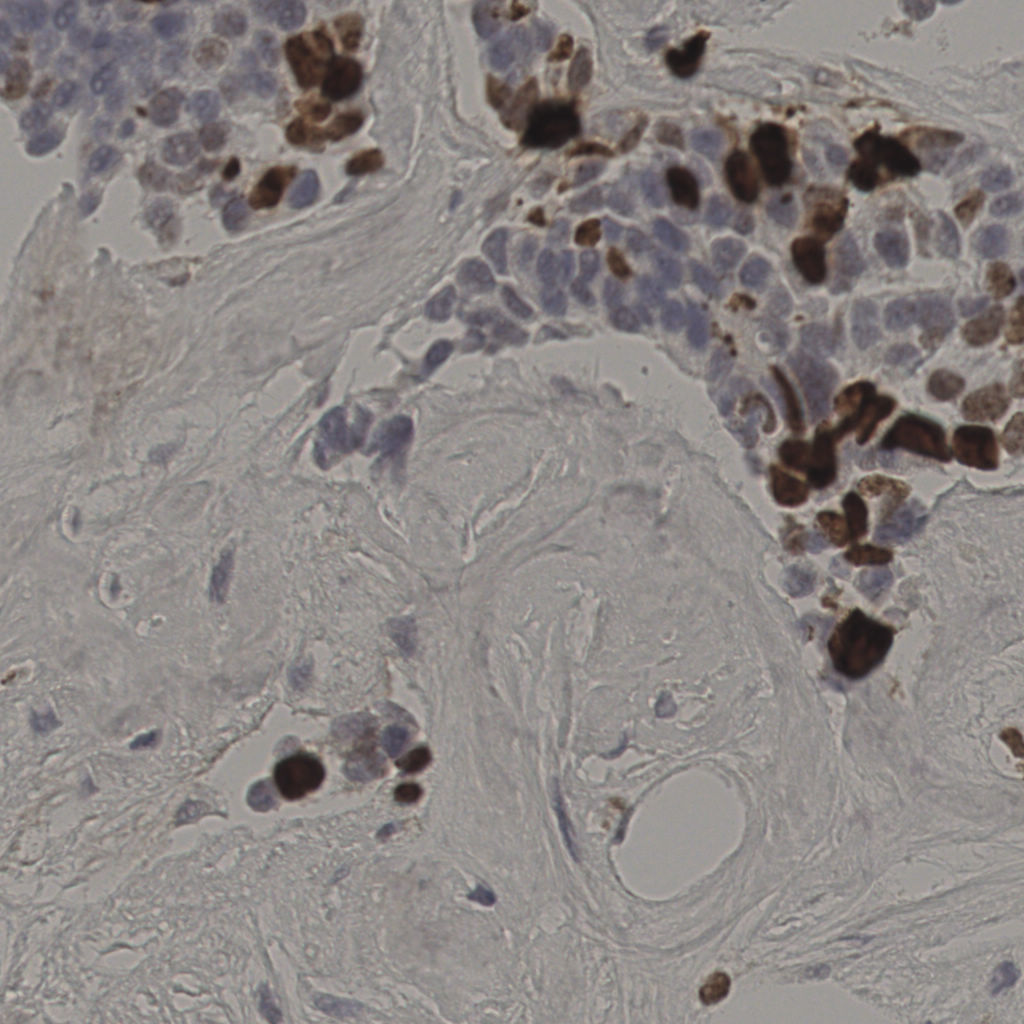

17.75%

Ki67 指数

阴 7986

阳 1723

缩略图

标记后

标记前